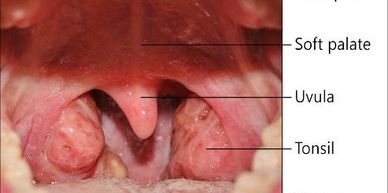

Tonsils and adenoids are part of the body’s immune system and play a role in defending against infections.

They are located at the back of the throat and behind the nose, where they help trap germs that enter through the mouth and nose.